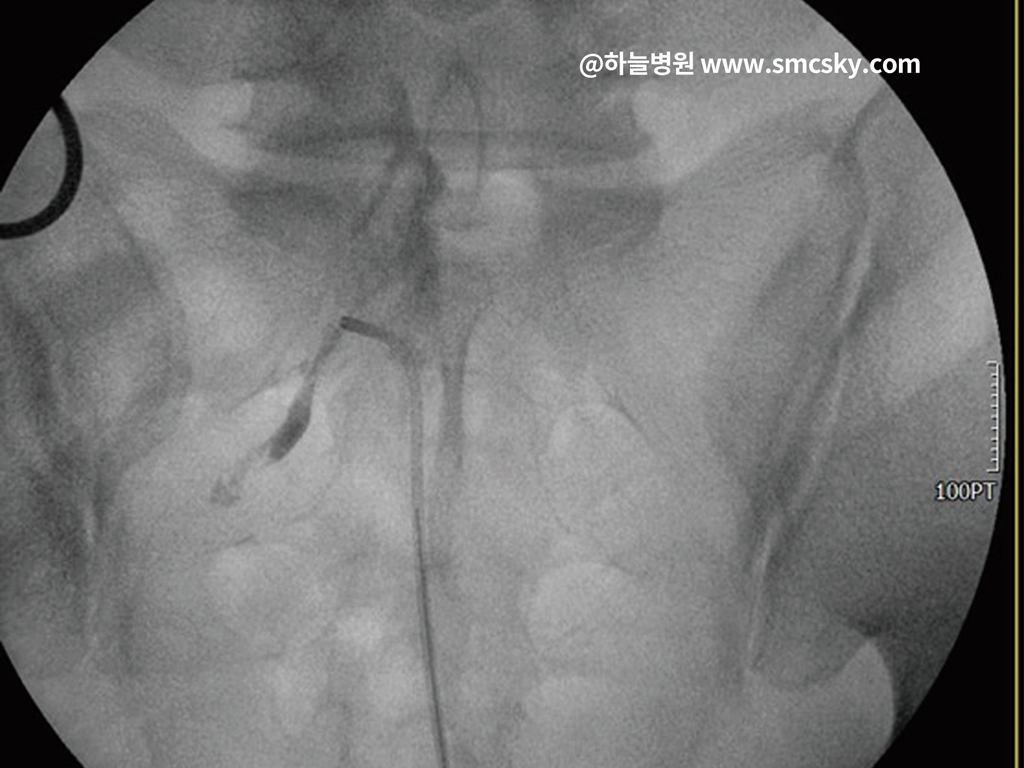

- 신경차단술과 같은 주사치료가 시행될 수 있습니다. 통증을 유발하는 신경 주변에 약물을 주입하여 염증을 빠르게 가라앉히고 통증을 즉각적으로 완화합니다.